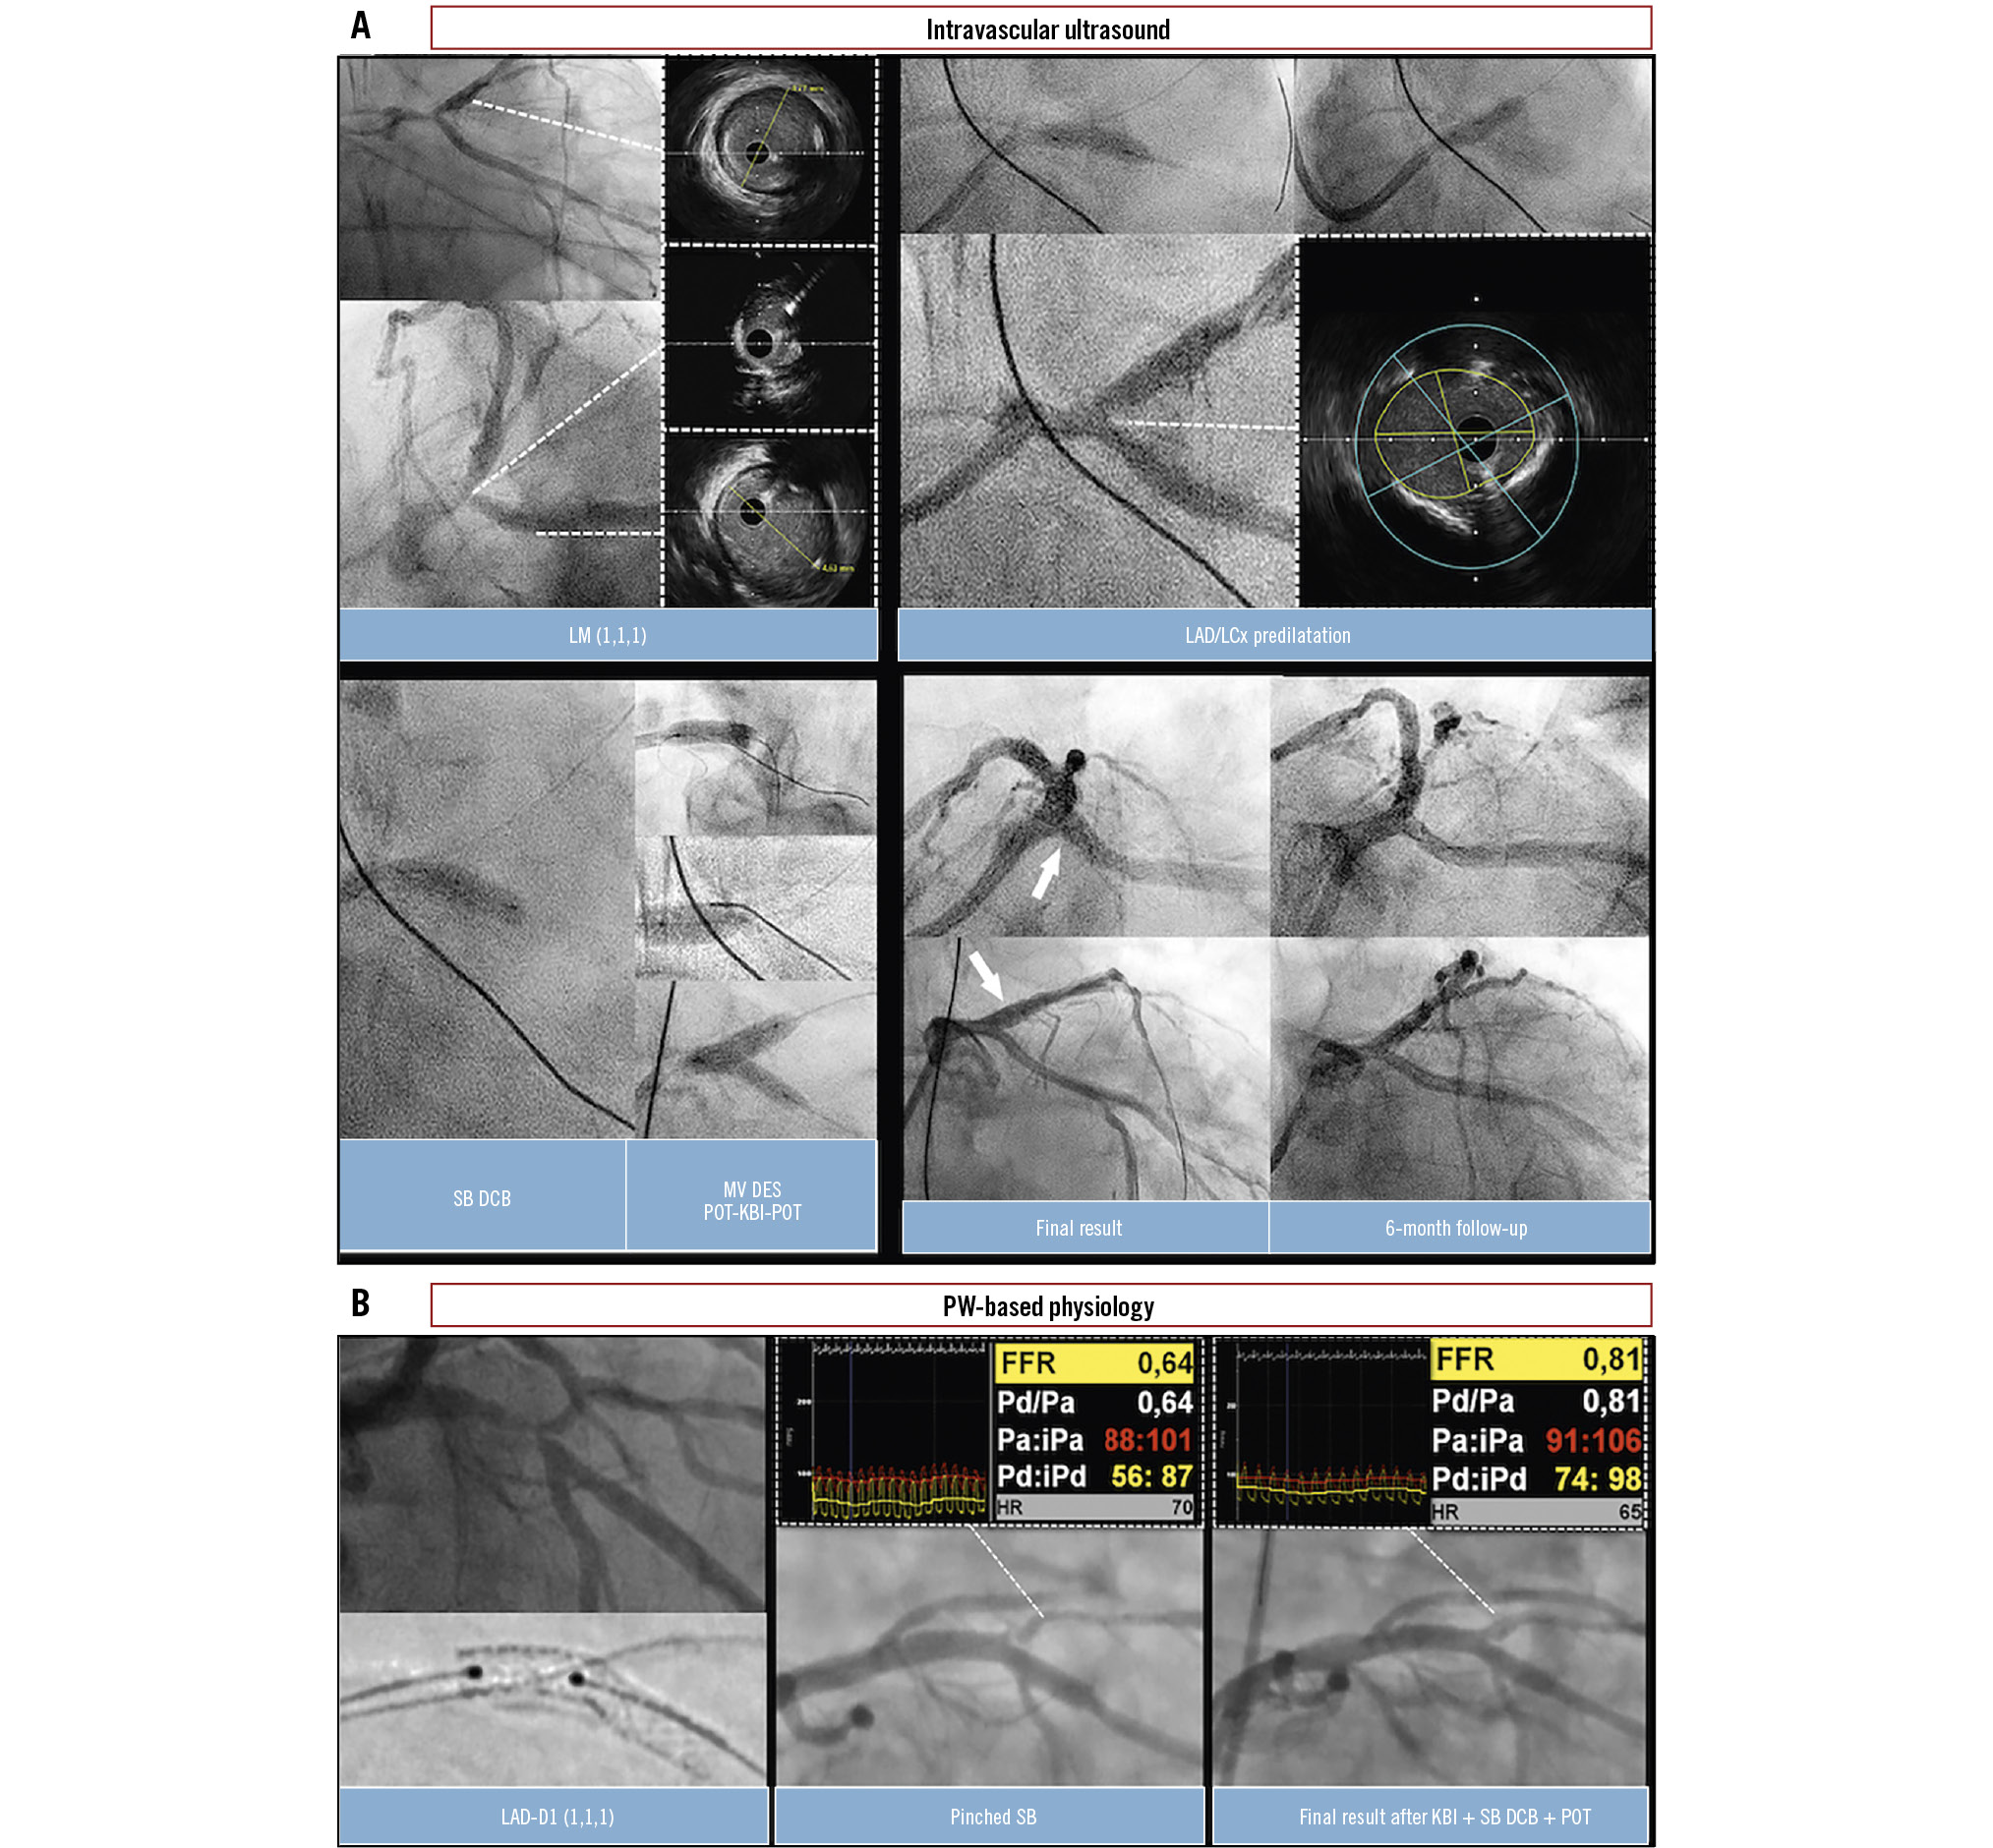

Figure 4. Coronary physiology and intravascular imaging guidance for a DCB/DES blended approach. A) A case of LM CBL (Medina 1,1,1). IVUS initially revealed a significant stenosis at the ostium of the LCx. Lesion preparation was performed using a 4.0 mm cutting balloon to predilatate the LAD, LCx, and LM. Following predilatation, the IVUS result in the LCx was deemed satisfactory, with restored flow and less than 30% recoil. However, IVUS assessment indicated unacceptable recoil in the LM segment. A 4.0×15 mm paclitaxel-coated DCB was first applied to the LCx for 30 seconds. Subsequently, a provisional DES implantation (5.0×16 mm) was performed from the LM ostium into the LAD. POT was then performed using a 5.5×6 mm NC balloon, followed by KBI (4.0 mm in the LAD, 3.5 mm in the LCx) and final POT. The final angiographic and IVUS results were satisfactory, showing minimal lumen areas of 14 mm² in the LAD, 7.7 mm² in the LCx, and 19.5 mm² in the LM. Three-month follow-up angiography confirmed a durable and favourable result of this blended approach. B) A case of LAD-D1 CBL (Medina 1,1,1). Following lesion preparation of the MV with NC balloons, a DES (3.5×22 mm) was implanted across the D1 using a provisional approach. POT was then performed with a 4.0×8 mm NC balloon. Subsequent angiography revealed a pinched SB with ischaemic FFR values (FFR 0.64) in the D1. After rewiring the SB, KBI was performed using 3.0 mm and 2.5 mm NC balloons, followed by inflation of a paclitaxel-coated DCB (2.5×20 mm) in the SB and the mandatory final re-POT. This strategy resulted in a favourable angiographic outcome and marked functional improvement, with FFR increasing to 0.81. CBL: coronary bifurcation lesion; D1: first diagonal branch; DCB: drug-coated balloon; DES: drug-eluting stent; FFR: fractional flow reserve; IVUS: intravascular ultrasound; KBI: kissing balloon inflation; LAD: left anterior descending artery; LCx: left circumflex artery; LM: left main; MV: main vessel; NC: non-compliant balloon; POT: proximal optimisation technique; PW: pressure wire; SB: side branch